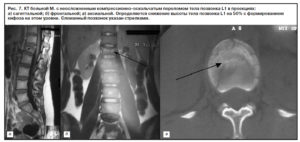

Компрессионный 3 степени перелом тела L1 позвонка